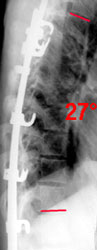

1 год после операции: угол по Коббу 23° (-64%), PTI=1,7 (-39%)

Использование топографии для оценки результатов оперативного лечения сколиоза

позволяет хирургу получить полное и детальное количественное описание всех изменений формы туловища и его ориентации в пространстве в ближайший и отдаленный постоперационный период.

Интегральный индекс PTI дает количественную оценку внешнего вида пациента в сопоставлении с гармоничной формой туловища. В приведенном примере пациентка имела PTI равный 2,8

(соответствует выраженным нарушениям формы туловища), а после операции - 1,7 (соответствует умеренным отклонениям формы туловища), таким образом коррекция по PTI

составила 39%, что соответствует среднестатистическому результату оперативного лечения с ипользованием CDI инструментария.